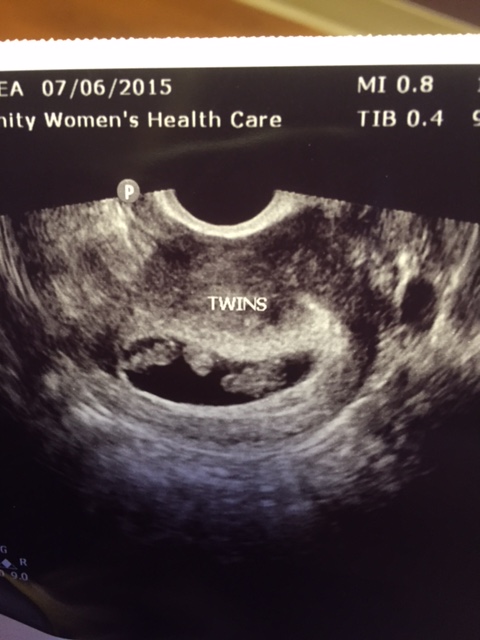

You guys. God is SO good. As are all of the amazing people in our life who love, support and pray for us. Every single one of our prayers were answered today. The babies are both doing great. They are BOTH measuring exactly the same at 8 weeks (1.53cm) which is actually a day ahead! Baby A's heartbeat was 148 and Baby B's (I really need to come up with better names for them!) was 160. I could tell right away that they have both grown SO much! We confirmed that there are two yolk sacs which as I mentioned before is a strong indicator that there is a membrane separating them. The yolk sacs are actually overlapping - one is in front of the other. They are the blob between the babies in the sono picture.

Enough of the BAD feelings and onto the good. Obviously when we think about the concept of this actually working out we are overcome with excitement. I'm not naive guys. I know having twins would be HARD. I know we'll be exhausted and overwhelmed and terrified for a million new reason when (not IF, but when) they get here. But truly this is a dream come true for us. Looking past the first trimester (which is obviously very hard for me) I know there's a lot of potential complications just with the pregnancy alone, not to mention the babies if they come early. I've done my research on the different type of twins. You can see from the sono picture below it appears both babies are in the same amniotic sac. If that is in fact the case that would make them MoMoTwins (monoamniotic). Basically they would share the same sac and placenta and they are very high risk due to the possibility of cord entanglement. However at this early stage it can be difficult to see the membrane that separates the sacs. It's more likely to see it between 8-10 weeks and a lot of times they won't be able to tell until your second trimester. In addition we saw 2 yolk sacs at our last ultrasound which is not a guarantee but a good indicator there will be two sacs. Honestly none of that is scaring me at the moment. All I am concerned with is that they BOTH keep growing. If God can just bless us with two healthy babies we will get through whatever difficulties and obstacles come our way. I know we can do this.

(That blob in between them is Baby B's yolk sac. You can't see Baby A's in this picture).

I don't even know how to start this post. Yesterday was definitely one of the most stressful days of my life. I was sick to my stomach all day with worry about the pending ultrasound. The day took forever and I couldn't concentrate on anything else. Work was a complete disaster. Finally it was time for me to leave and head to the appointment. D was waiting for me in the parking lot. When we got there I had to pee of course so I went back to use the restroom and saw my doctor when I was walking out. She took one look at me and dropped everything and came over to give me a hug. She just told me to take a couple deep breaths and they'd get me back there as soon as possible. I returned to the waiting room and we sat there for what felt like forever. Finally they called us back and it was a new sono tech that I hadn't met or dealt with before. She asked how far along I was and I immediately just started spilling our whole story to her. Like I needed to prepare HER in case it was bad news. She left so I could get undressed and I was literally shaking all over. When she finally came back and we got started as soon as she put the wand in I was searching the screen for the sac, which I saw right away and I could see a small white blob in it. As she was zooming in she said "Oh I see a little heartbeat". I immediately got tears in my eyes and said "You do??" She confirmed and then I will never forget what happened next..........

She said "And there's the other one....I thought I saw two".

Silence. Confusion. Finally I was like "Are you serious?" And she said "Yep, here's the first baby and there's the second. I see heartbeats for both but we will measure and listen to them separately". At some point I said my husband's name in a panicked tone and I remember him saying "It's okay, it's okay". I'm not sure either of us said much after that. I'm pretty sure we're still in shock. I just cannot believe it. Twins. Naturally. Wow.

Yesterday I was 6 weeks 6 days. Baby A was measuring 6 weeks 2 days with a heartbeat of 115 (they said they just wanted to see it over 100 at this point). Baby B was measuring 6 weeks 5 days with a heartbeat of 128. Obviously I'm a little concerned about baby A measuring behind but no one else seemed to be at all. I am just praying so hard that he or she continues to grow grow grow this week.